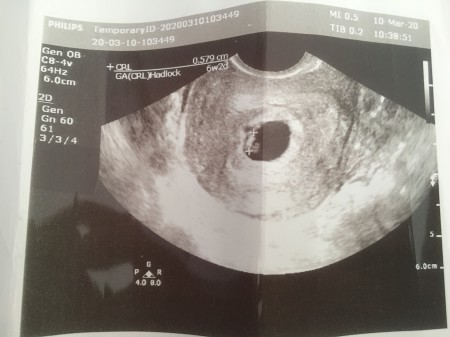

saat 11 de randevum var annemle gıdıcez bana dua edın kese bebek goruncekmı cok merak edıyorum 6+2 bugun ınsallh bı sıkıntı olmaz :(

image

cok şukur rabbıme :)

cok sukur usten kese gorundu alttan da bebek ve kalp atısını duydum :)

kese gorundu normal muayneyle alttan baktı bebegıde kalp atısınıda duydum cok sukurrr :)

kese usten görüldü alttan muayneylede bebısı be kalp atısını duyduk :) rabbımr cok sukur

gordum cok sukur ustten keseyı gorduk bebek kucuk oldugu ıcın gorunmedı altan muayneyle bebıste kalp atısıda duyuldu :)

6 haftalık suan ama 5 haftalık dedı keseyı gordu bebegı goremeyınce ben endıselendım alttan baktı bebegıde kalp atısınıda duydum cok şükür